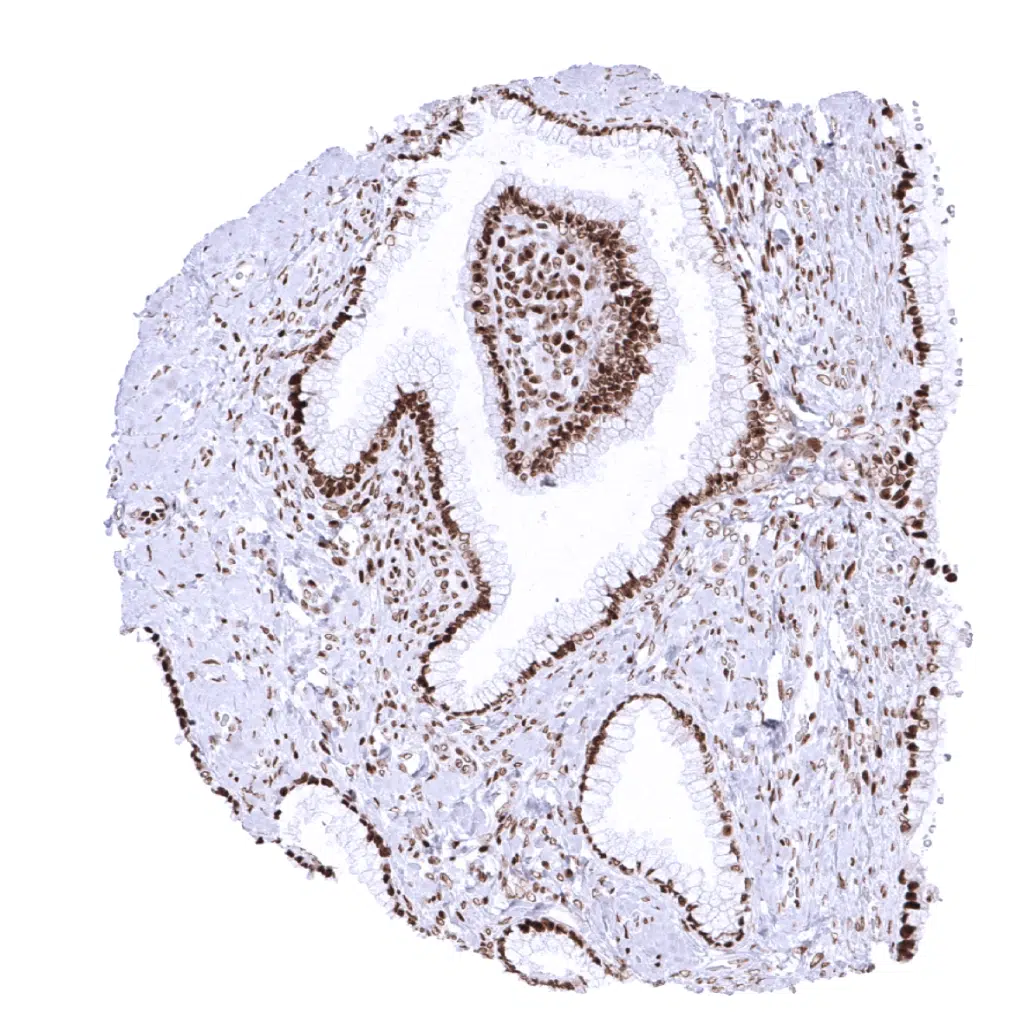

Prostate